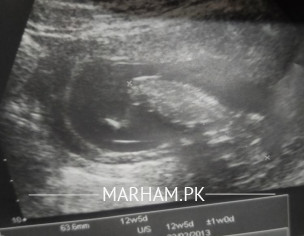

slam doctor.. attached is my ultrasound report.. I'm in 4th month of pregnancy... spotting and bleeding hy.. doc said oval neechy hy apki.. damage h is liy bleeding hy.. bedrest suggest ki.. medicine li hn lekin abhj tk wese e hy... today i learned that there are 4 grades of low lying placenta.. can you tell what grade this report showing... and what can i do to avoid this low lying position.. any exercise or something else.. jazakAllah

At 4 months we don’t categorize it in 4 types , we call it just low lying , secondly it cannot be treated by any exercise , sometimes as the pregnancy grows and uterus size increases it shifted upwards with growth of the uterus but sometimes it remains and we call it placenta previa after 20-24 weeks .